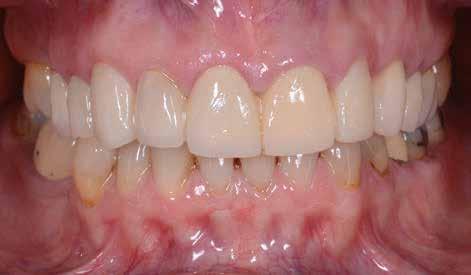

A páciens elégedett volt a végleges restaurátumok színével, formájával és méretével. A kezelés végeredménye kielégítette az esztétikai elvárásait (9. ábra). A frissen átadott restaurátumok épségének megőrzése érdekében a páciens számára éjszakai fogvédősínt készítettünk. A páciensünk a négyéves kontrollvizsgálat során is nagyon elégedett volt a kezelés eredményével. A korábban meglévő fekete háromszögek eltűnésének különösképpen örült (9. és 10. ábrák)

9. ábra. A beavatkozás után, valamint a 4 évvel később látható állapot. (A): Egy héttel a ragasztás után készült felvétel. (B): A négyéves kontroll alkalmával készült felvétel.

Jelen esettanulmányban három meglévő technika kombinálását és továbbfejlesztését mutattuk be: washi papír használatával történő belső fogfehérítést, nyomtatott sebészi sablon által vezetett ínyplasztikát, és a fogakra ultravékony földpátkerámia héjakkal történő ellátását. E bonyolult eset kezelése során – minimálinvazív megközelítés mellett – kiemelkedő esztétikai eredményt sikerült elérni.

Az alapos tervezést követően végzett restauratív beavatkozások során sikeresen kombináltuk a washi papírral végzett belső fogfehérítést, a 3D nyomtatott sebészeti sablonnal és elektrokauterrel végzett ínyplasztikát, továbbá az ultravékony földpátkerámia héjakkal történő ellátást. A kezelési terv követésével el lehetett érni a kívánt esztétikai eredményeket, amelyek már 4 éve stabilnak bizonyultak.